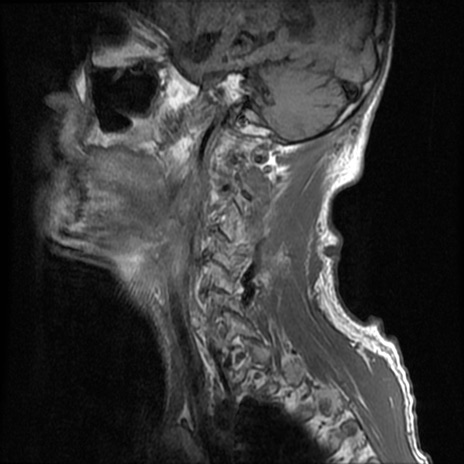

症例46 頚椎MRI T1WI(矢状断像)

頚椎MRI

T2WI(矢状断像)